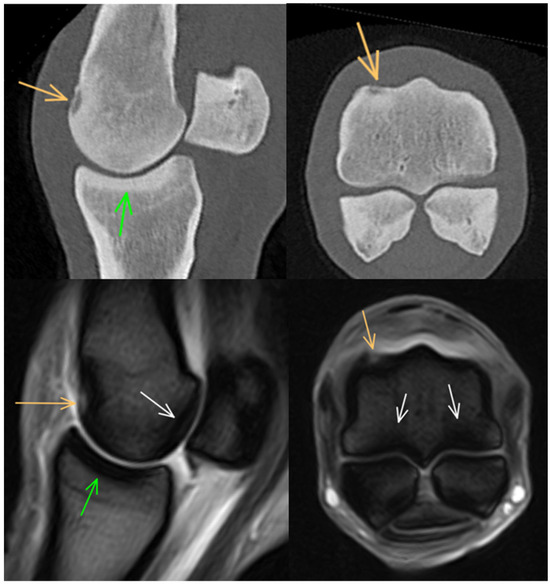

3.3. Proximal Sesamoid Bones